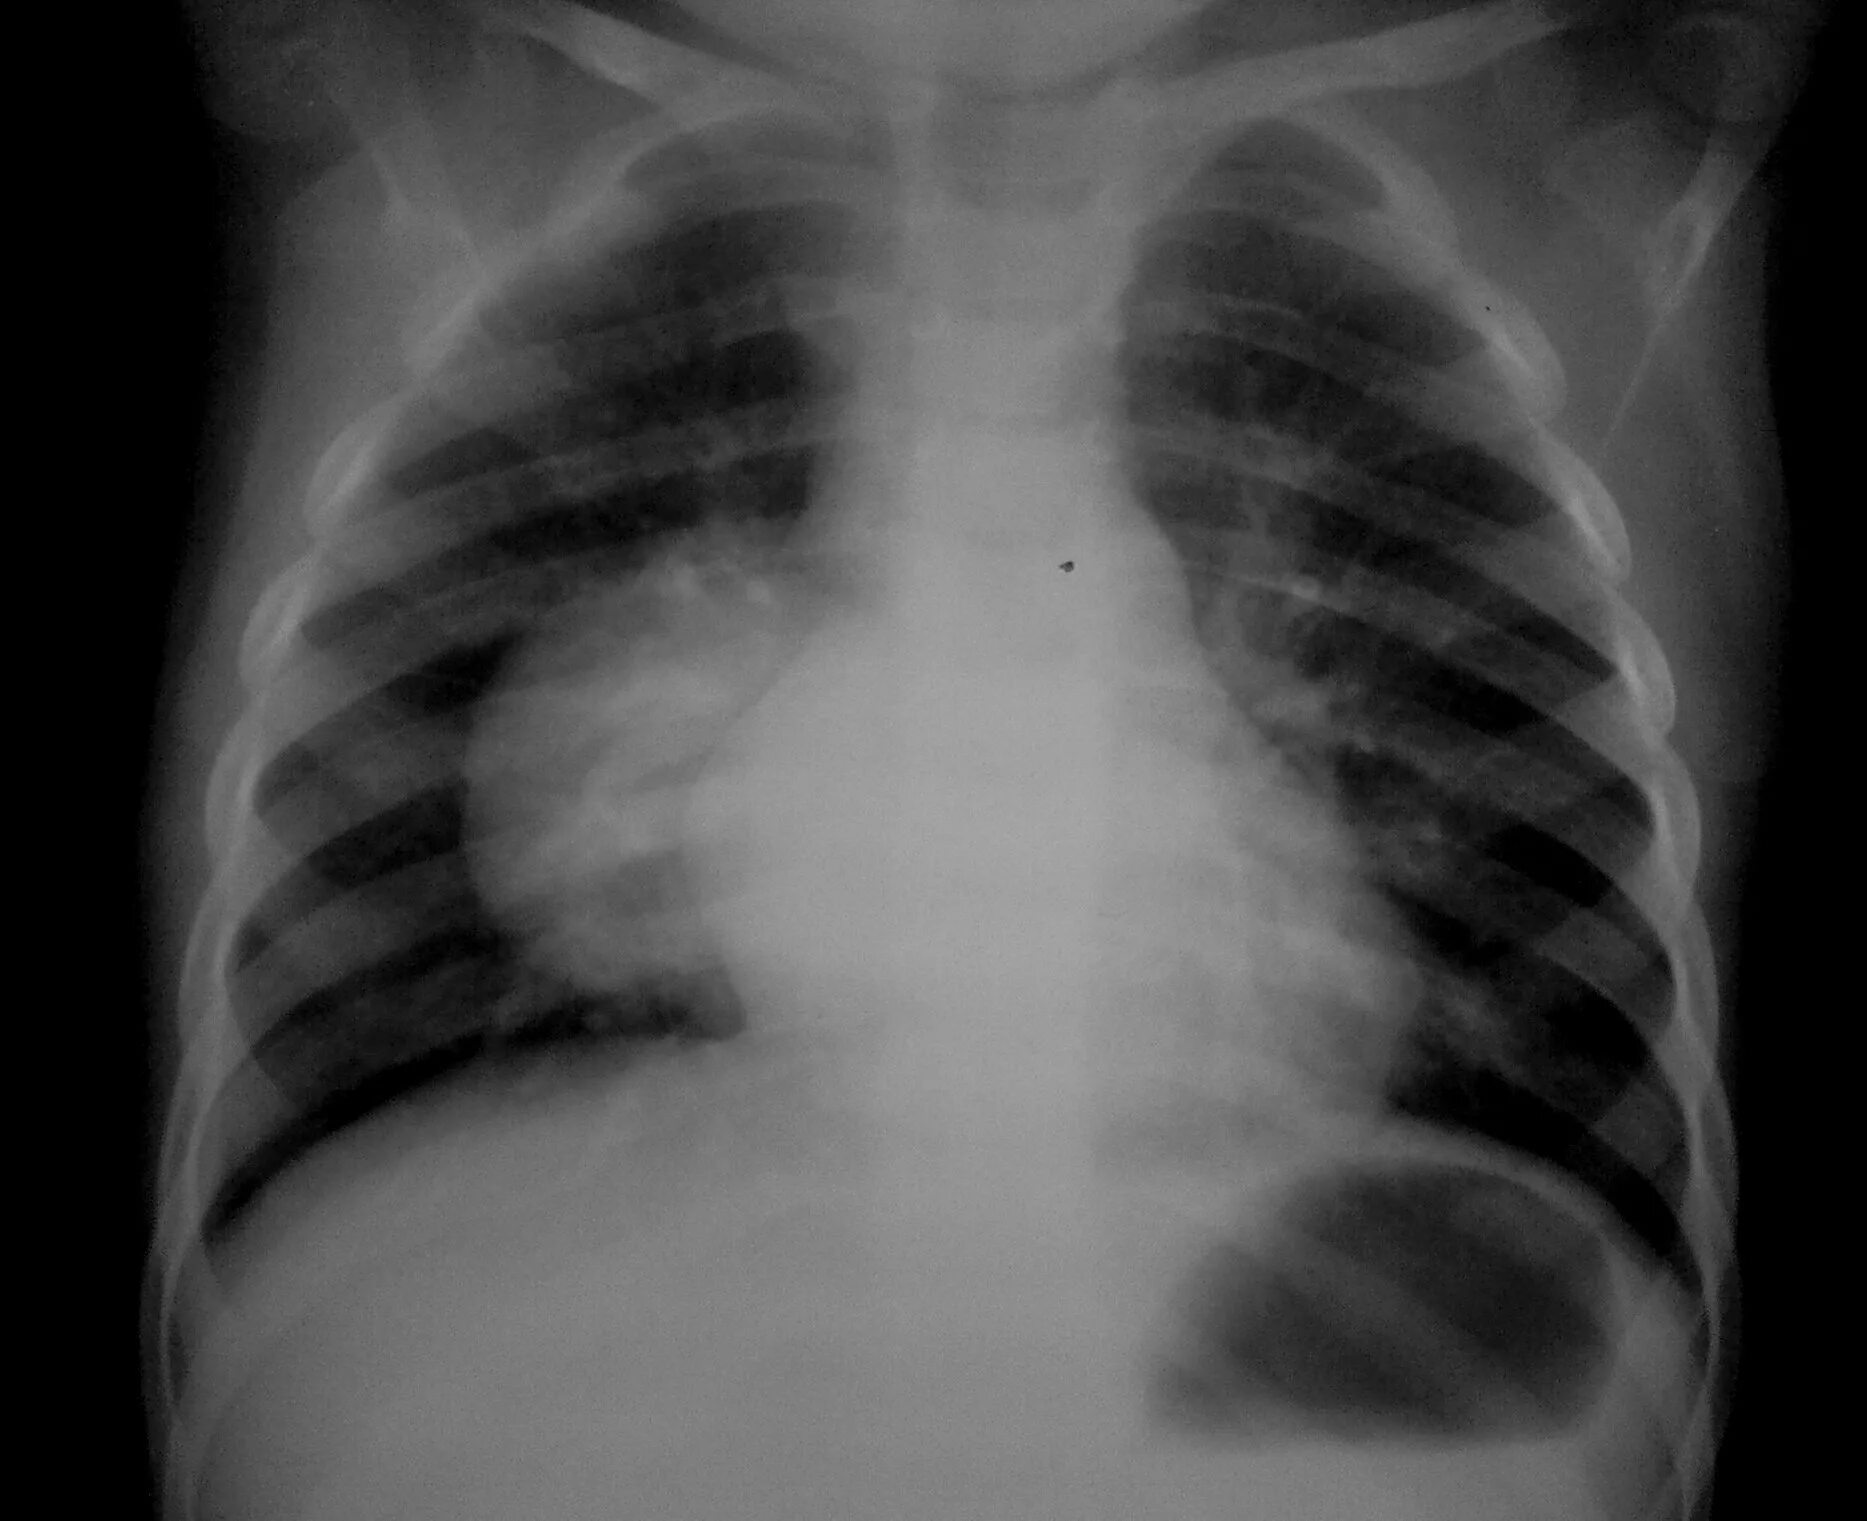

Помощь при туберкулезе легких